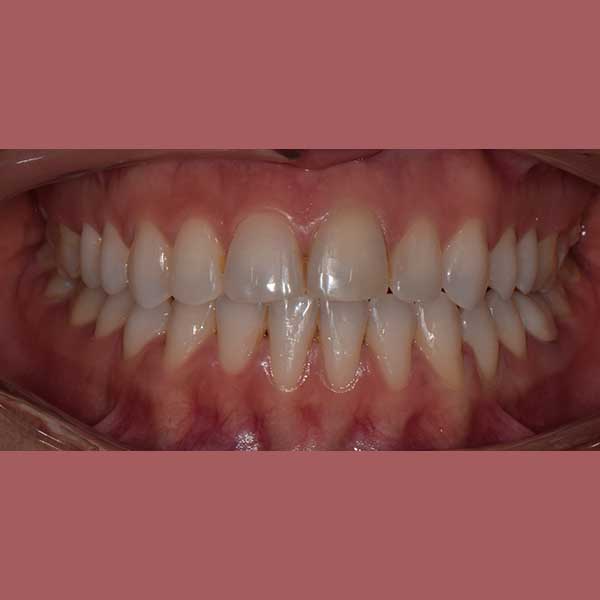

This patient has suffered from spaces between her lower teeth due to an unknown reason, and by examining the teeth, I found that the gums were healthy and fixed braces were installed and the spaces were closed successfully in addition to the paving of the upper teeth successfully as well.